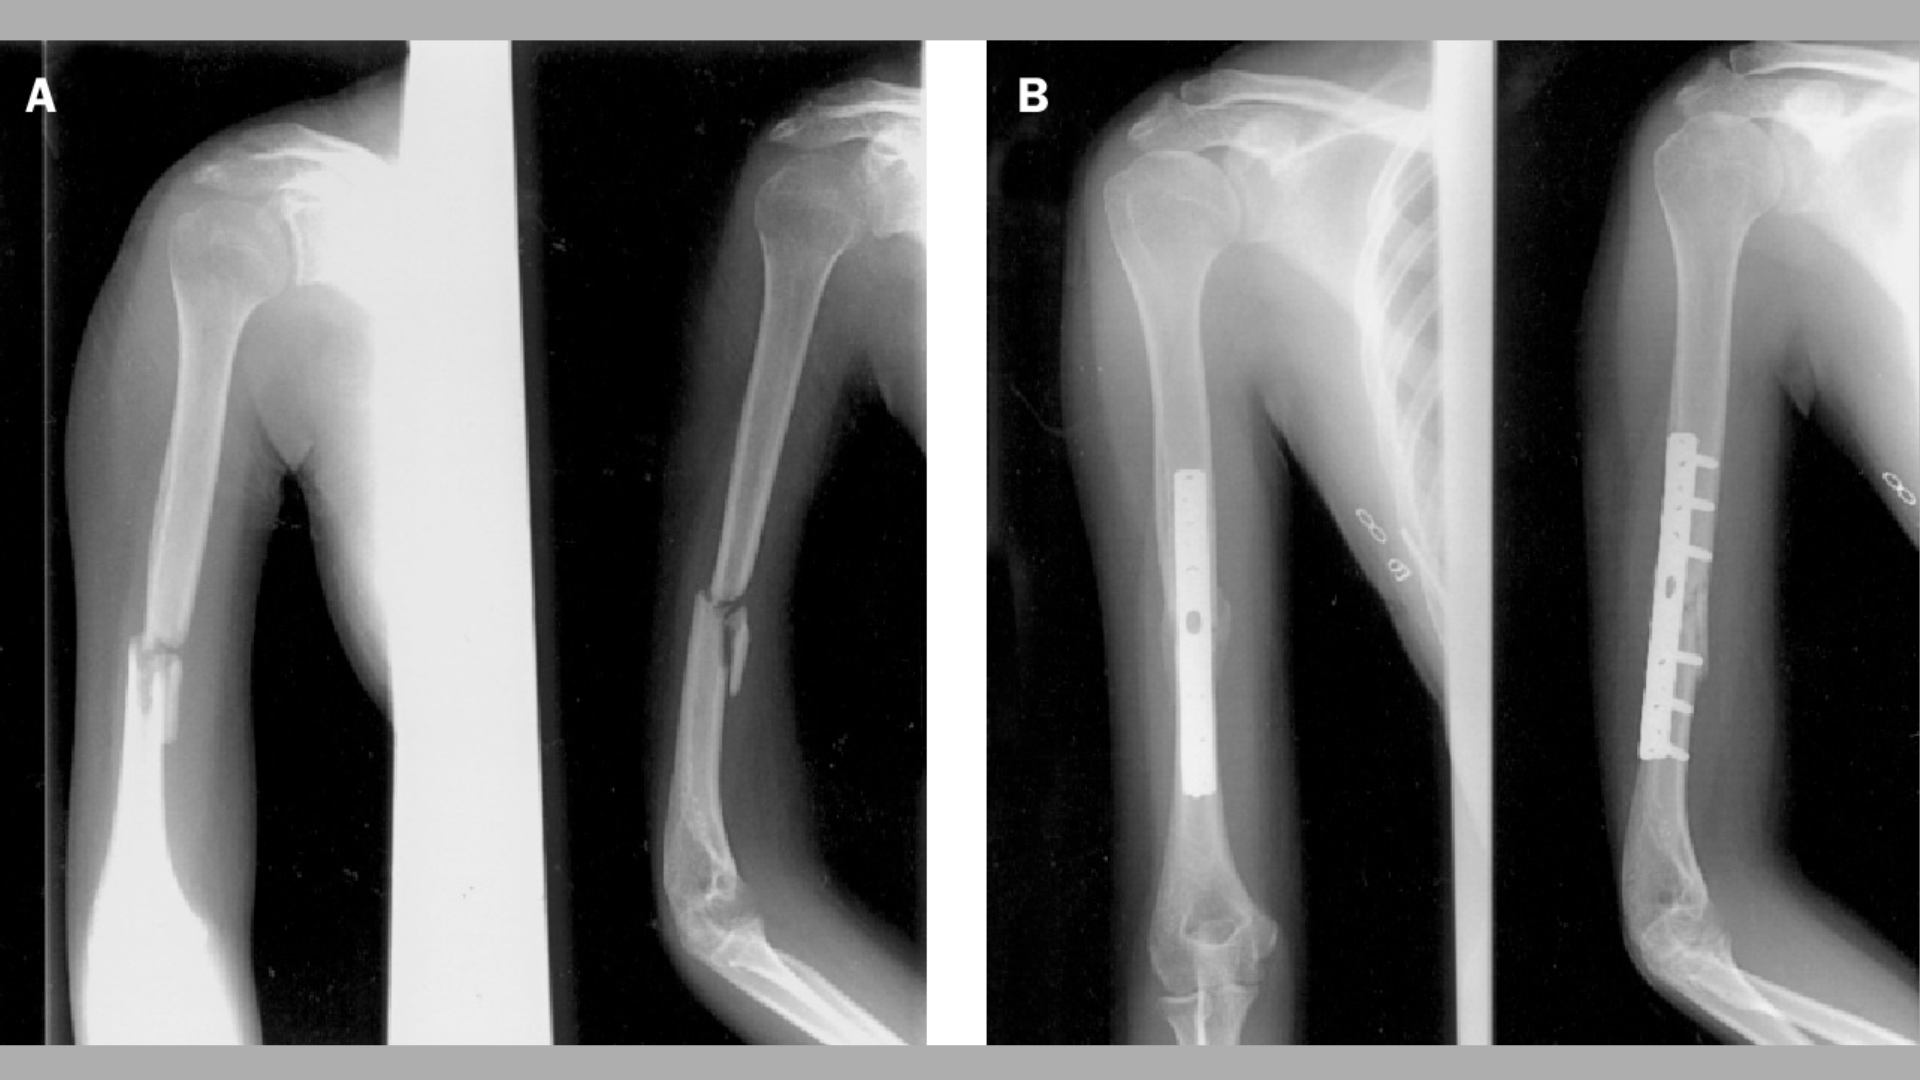

Phẫu thuật được chỉ định trong các trường hợp gãy xương di lệch nhiều, gãy hở, gãy không vững hoặc có kèm tổn thương mạch máu, thần kinh. Ngoài ra, những trường hợp thất bại với điều trị bảo tồn cũng cần chuyển sang phẫu thuật. Hai kỹ thuật phổ biến nhất là kết hợp xương bằng nẹp vít (ORIF) và đóng đinh nội tủy. Mỗi kỹ thuật được lựa chọn dựa trên vị trí, mức độ gãy và điều kiện mô mềm xung quanh.

Phẫu thuật giúp phục hồi giải phẫu chính xác, ổn định ổ gãy tốt hơn và cho phép bệnh nhân sớm vận động chi. Tuy nhiên, đây là phương pháp xâm lấn, tiềm ẩn các nguy cơ như nhiễm trùng, tổn thương thần kinh quay, hoặc lỏng dụng cụ kết hợp xương, đòi hỏi theo dõi hậu phẫu sát sao và chăm sóc chuyên khoa.